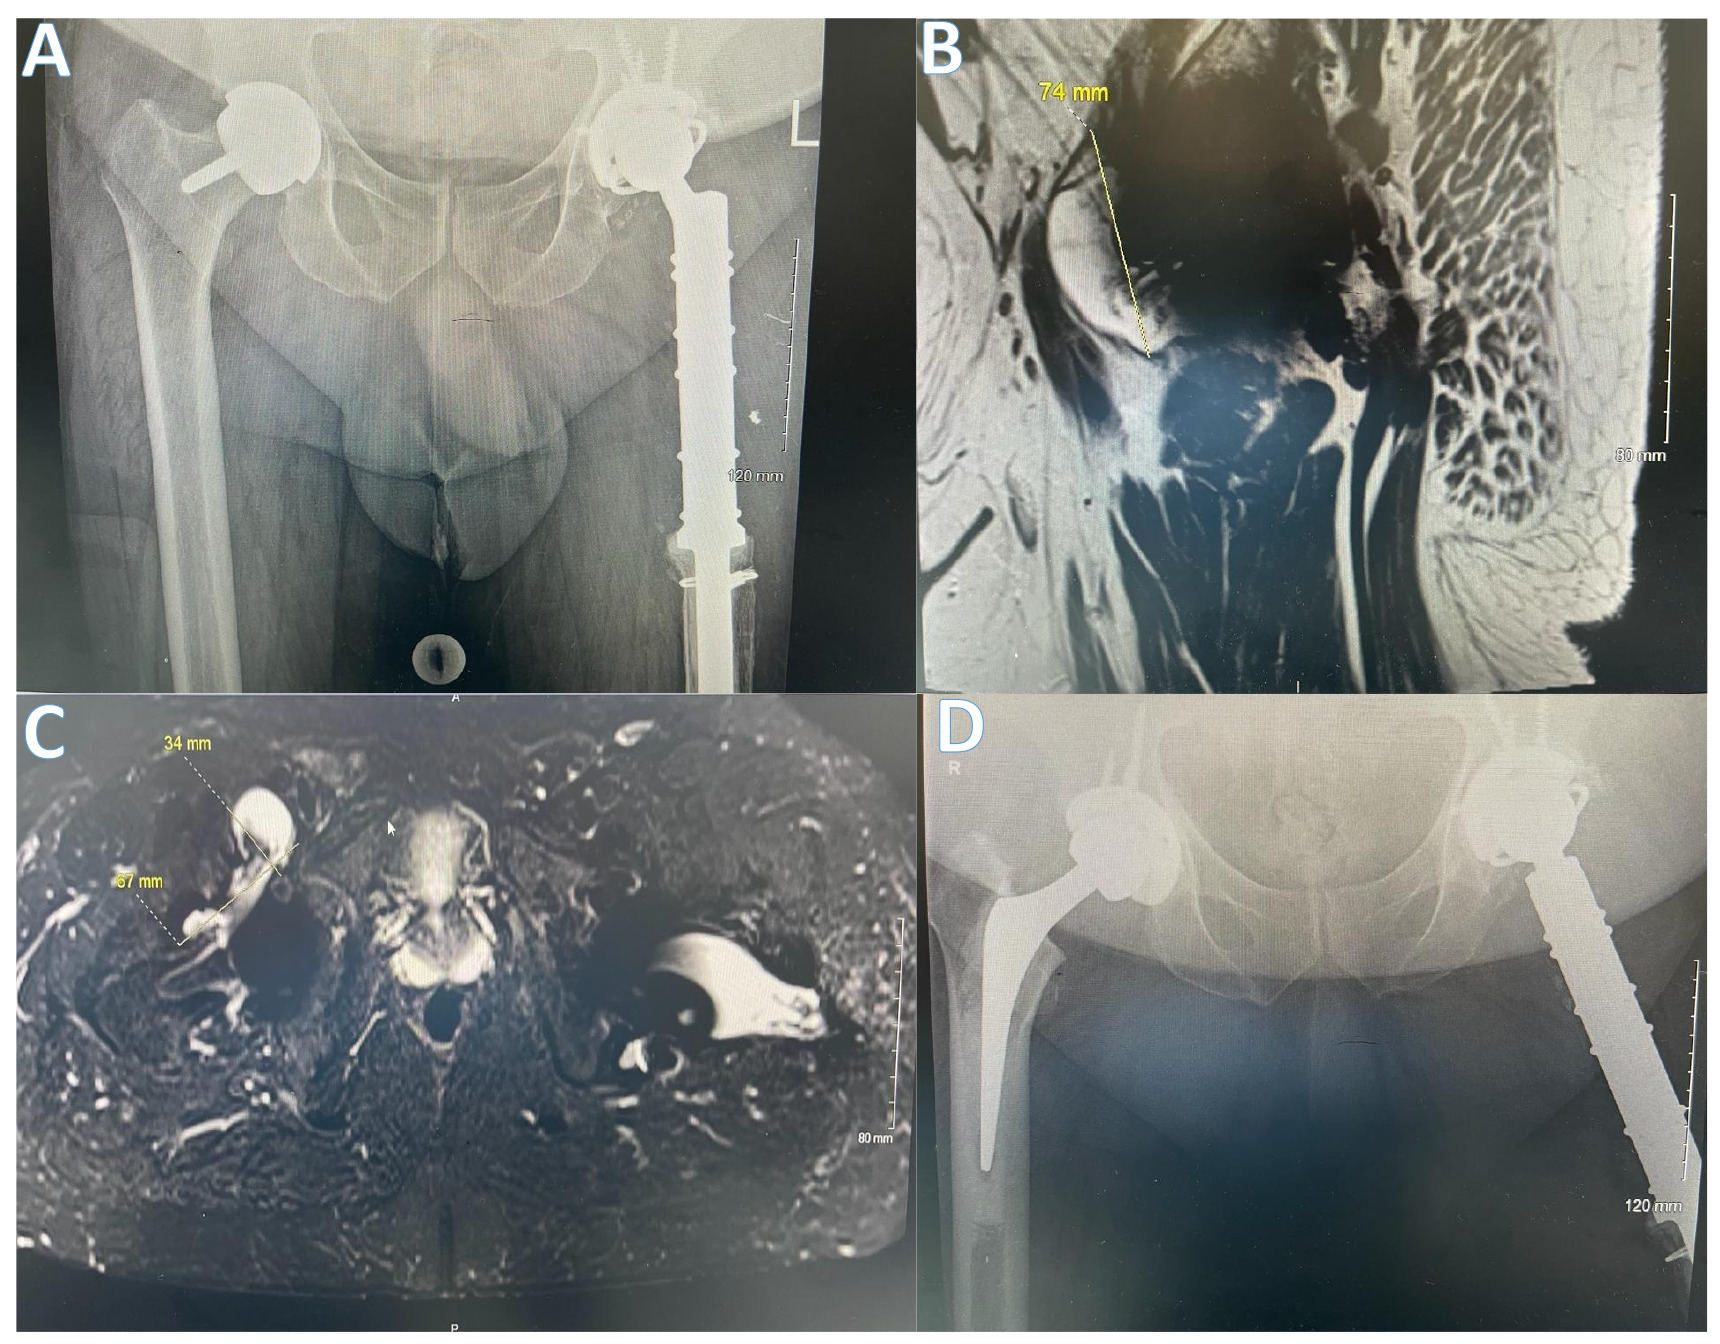

In addition, patients with developmental dysplasia of the hip (DDH) are generally considered unsuitable for HRA. This cohort of patients’ anatomy involves abnormal femoral and acetabular morphology such as increased anteversion, as well as a shallow, dysplastic, and more inclined acetabulum therefore, making it more challenging to optimise the position of the cup and avoid edge loading. The Australian NJR has reported a 20.3% revision rate in DDH patients undergoing HRAs over a ten-year period; in comparison, patients with osteoarthritis (OA) as a primary diagnosis had a 9.3% revision rate. It is worth noting that when a cup is implanted >10 degrees away from the ideal 45-degree inclination, the risk of metal-on-metal pseudotumour is tripled.43 (Figure 3) Therefore, the ideal candidate for consideration for a HRA is a male aged under 55 years with primary osteoarthritis and an adequately sized femoral head in the absence of a history of DDH, avascular necrosis or inflammatory arthritis (Figure 4).